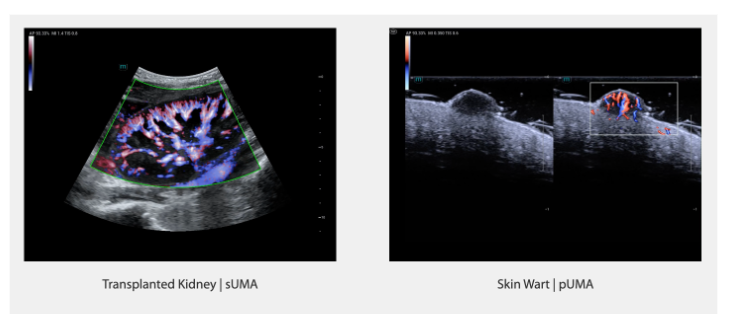

HiFR CEUS

HiFR CEUS (контрастное ультразвуковое исследование с высокой частотой кадров) обеспечивает ультрабыструю визуализацию по сравнению с традиционными методами. Детально фиксирует особенности кровоснабжения органа в артериальной фазе, улучшает диагностику опухолей и позволяет изучить структуру кровоснабжающих сосудов.

-

в 6–8 раз быстрее, чем традиционное обследование CEUS

-

Исследование особенностей кровоснабжения опухолей

-

Более четкое отображение кровотока в артериальной фазе

- Метастатическая карцинома печени